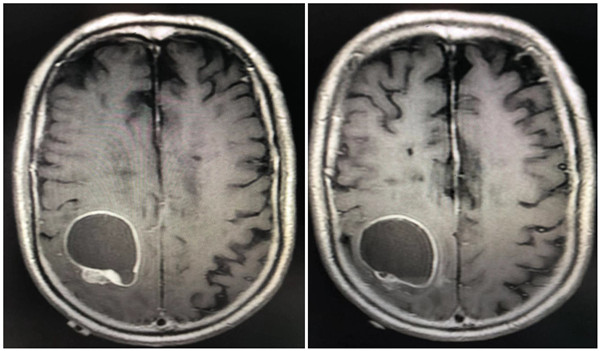

患者李某某、男性、79岁、右利手,以“左侧上肢活动不灵2周”为主诉入院,入院后经检查诊断为:右侧顶叶颅内占位。考虑到患者高龄心肺功能较差,完善各项相关检查并经麻醉、心内科会诊后将患者一般状况调整稳定。在巩守平教授、屈建强主任,杨庆余教授的主持下进行了术前讨论,由于病灶位于功能区,术前行脑功能成像,确定病变与重要传导束的关系,患者高龄为了减少损伤,术中行电磁导航定位,量体裁衣确定手术切口,病灶囊性为主,为了确保术中不损伤重要功能区,暴露病变后采用超声确定病变位置,电生理确定重要功能区,然后由非功能区造瘘进入病变切除肿瘤。确定方案后,12月11日在气管插管全麻下行颅内占位切除术。

术前颅脑核磁共振